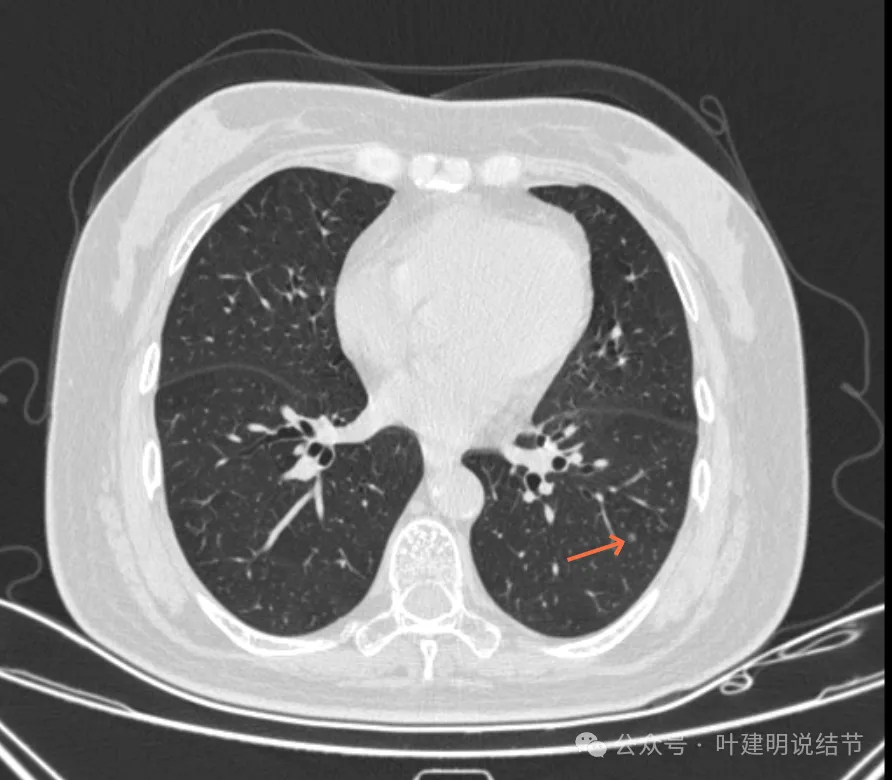

病灶19-20:两肺淡磨玻璃结节,轮廓较清,小但边界清楚。

病灶21-22:两肺淡磨玻璃结节,轮廓较清。

病灶23-26:两肺微小淡磨玻璃结节,轮廓较清。